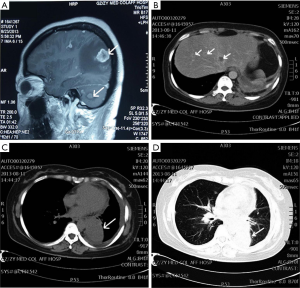

On November 27, 2012, a 47-year-old female was diagnosed as the left lower lobe adenocarcinoma stage IV (T4N2M1, pleural metastasis) via lung biopsy and was detected wild-type EGFR and 18% ALK gene rearrangement from paraffin section. Subsequently, the patient selected standard chemotherapy as adjuvant treatment considering the economic condition. Hence, from January 8, 2013 to August 29, 2013, seven cycles of standard chemotherapy were administered including three cycles PC regimen (paclitaxel, 150 mg/m2 plus cisplatin 75 mg/m2), two cycles PP regimen (pemetrexed, 500 mg/m2 plus cisplatin 75 mg/m2), one cycle DP regimen (docetaxel, 75 mg/m2 plus cisplatin 75 mg/m2) and one cycle NP regimen (vinorelbine 30 mg/m2 plus cisplatin 75 mg/m2) along with Endostar (Figure 1).

Because of the aggravated side effects, the patient refused to take systemic chemotherapy. However, the primary lesion of left lung still existed and metastases developed in brain (Figure 2A) from magnetic resonance imaging (MRI) and in lungs and liver (Figure 2B) from CT scan. Hence, crizotinib targeted drug therapy was recommended. Simultaneously, the patient was diagnosed with lower left lung adenocarcinoma, stage IV, along with bilateral lung, pleura, brain and liver metastases (Figure 2).